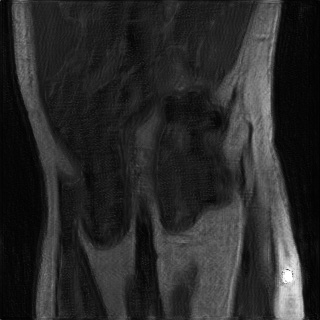

Accelerated MRI enhancement: The FastMRI [3] database consists of more than 1500 multi-coil diagnostic knee MRI scans and corresponding emulated single-coil data. Our experiments are based on a subset of nearly 800 coronal proton-density weighted scans without fat-suppression from the official train and validation single-coil releases. We remove of the patients for evaluation and split the remaining patients into input and target data. While the target domain consists of slices from fully-sampled MRI scans, we consider 4x acceleration (only of k-space measurements) for the slices by using the subsampling scheme discussed in [3, 4]. This yields 7.1k train slices for input and 6.9k for target. We are aware that enhancement of accelerated MRI can also be considered as a supervised task since generation of paired instances is feasible. However, this experiment should demonstrate possible applicability of the proposed framework to inverse problems in general.

In Table 2 we observe for the accelerated MRI enhancement task on FastMRI that our method UAPI significantly outperforms other benchmark on unaffected test data but gives modest accuracy when additional noise and perturbed pixels are added. Figure 4 shows the superior performance of CUT in terms of the PSNR metric for noisy data. This is quite interesting since that has not been the case for the previous modality propagation application. The task of accelerated MRI enhancement strongly differs from the other two applications. While the goal of modality propagation and MRI-to-CT synthesis is to come up with a completely new image, the aim of accelerated MRI enhancement is to improve quality of a already existing image. In fact, the methods cycleGAN, UGAC, gcGAN, PI and UAPI depend on a rather simple U-Net [34] implementation and a standard DCGAN critic [35] with the aim to demonstrate plausibility of different transfer approaches on easy-to-implement frameworks. The CUT method is a benchmark where the publicly available source code had to be used, consisting of a ResNet-based generator [11] and built-in data augmentation techniques that may better compensate for noisy input data. Nevertheless, our methods PI and UAPI seemingly achieve better results compared to the U-Net based benchmarks. We will take up investigation of robustness of our methods in combination with different network architectures as a future goal.

4.4 Qualitative Evaluation

In Figure 5 we analyze the prediction quality of our and compared approaches in a qualitative way. Considering modality propagation in MRI, we see that usage of uncertainty-aware patch invariance (UAPI) gives a better detailed weighting of the cerebrospinal fluid in the middle of the brain. In general, employing patch invariance yields better preservation of fine structures. This observation also applies to accelerated MRI enhancement. In particular, CUT and UAPI provide comparatively sharper knee images with more high-frequency details than the other methods.

Additional to improved accuracy we demonstrate the efficacy of estimating the scale maps with the proposed method. The input-dependent non-negative scale maps are derived from the second output branch , see (9). Indeed, the predicted scale maps are able to model uncertainty inherent from data. This can be observed in Figure 8, where in addition to the transferred images also the predicted scale maps and the absolute residuals between predicted and ground truth images are displayed. Obviously, uncertainty is relatively greater in regions with higher residual values. From the scale maps it can be deduced for which positions the generator is comparatively uncertain in its prediction, such as the cerebral cortex and eye sockets in head MRI or the lateral knee ligaments in knee MRI.